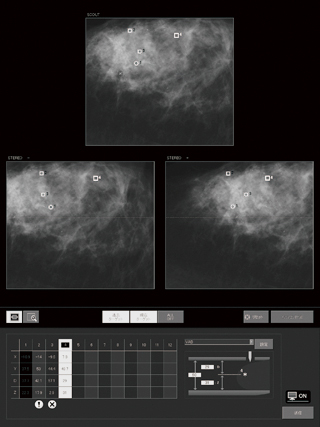

- スカウト画像でターゲットを選択することで,ステレオ画像上にガイドラインを表示し,位置決めをサポートします。